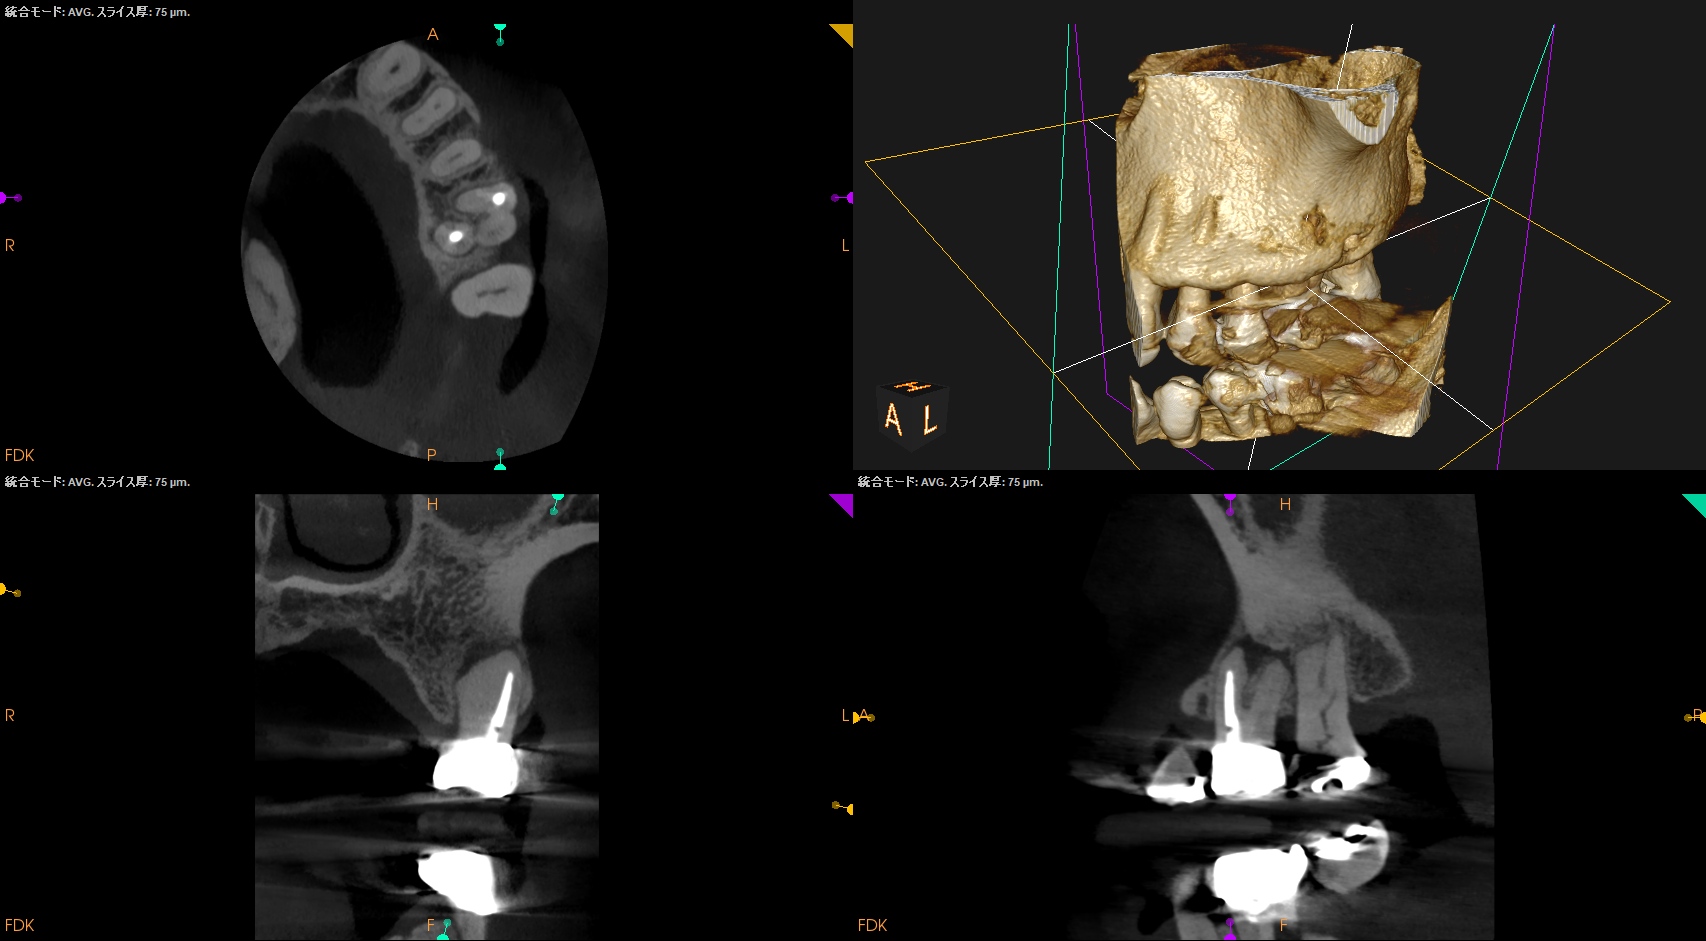

MB,DBは外科時には以下のようになる。

DBは楽だが、MBは頬舌径が7.4mmでMB1, MB2があるという…難ケースだ。

逆根充後にPA, CBCTを撮影した。

MB

DB

P

B